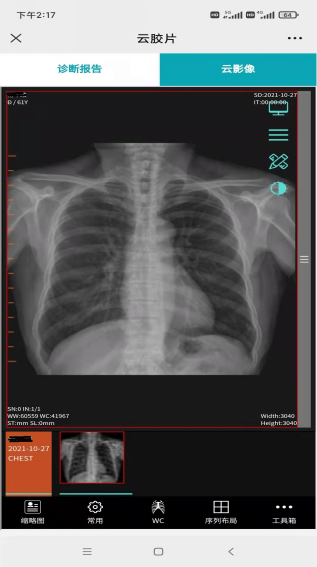

醫學影像遠程會診實現服務新提升。2021年7月初組建區域 “云”影像診斷中心,依托健康數據云平臺優勢,構建閻良區域醫學影像大數據云平臺。平臺以閻良區人民醫院為中心,聯通6個街道衛生院,為基層衛生院提供線上診斷,群眾無需奔波就可享受二級醫院的診斷水平,節約了醫療資源、降低了醫療費用。

“云”膠片替代傳統影像膠片

手機查看拍片影像

遠程診療高效協同。5G技術為疾病診斷、監護和治療等提供的信息化、移動化和遠程化醫療服務,實現了遠程會診、遠程影像、遠程心電、雙向轉診等業務高效協同服務,既促進了優質醫療資源共享下沉,又提升了醫院運營效率和診療水平。今年以來,區域“云”影像診斷中心累計診療報告數超7500例,遠程心電數累計達11.9萬次,群眾就醫體驗持續改善。